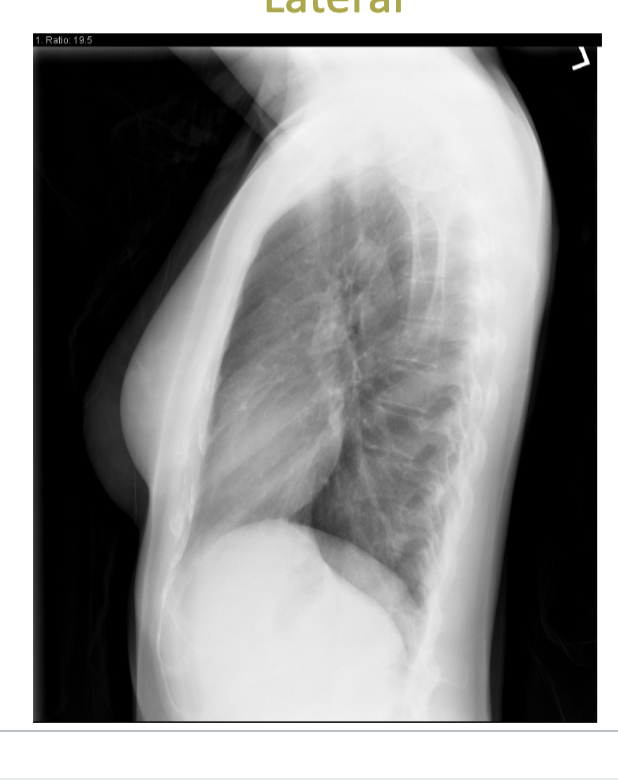

which type of projection is attached?

lateral

2, upright AP and Lateral (AP common in ICU), have to perform with good inspiratory hold (1 view is NEVER enough)